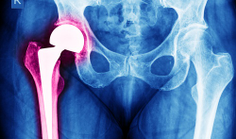

_ Hip Health Hip ReplacementA New Path for Patients Needing A Second Hip Replacement By Jane Farrell articleA newer type of artificial hip could be a good option for patients who need their original replacement taken out, … Read More→

_ Hip HealthDual Mobility Hip Replacement Reduces Risk of Dislocation By Sondra Forsyth articleMore than 330,000 total hip replacements are performed in the United States each year. Overall, it is a highly successful … Read More→